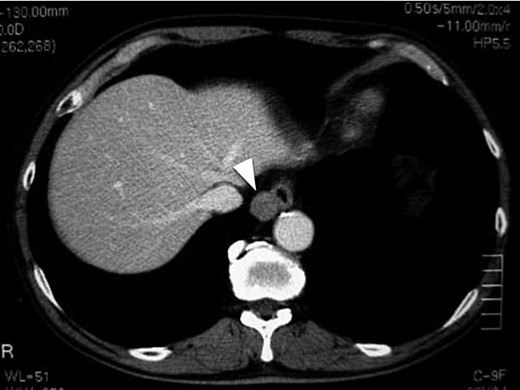

A 62-year-old male was found to have a well-demarcated mass with a smooth surface at the right side of the lower esophagus by chest computed tomography (CT) upon medical check-up (Fig. 1). Routine laboratory data and the serum levels of tumor markers were within normal limits. Positron emission tomography (PET) revealed the accumulation of 18F-fluoro-2-deoxyglucose (FDG) at the tumor. The maximum standardized uptake value was 4.0, increasing to 4.8 in the late phase. Upper gastrointestinal endoscopy revealed no distinct mucosal abnormalities or no evidence of tumors. Endoscopic ultrasonography showed a mass ∼2 cm in diameter arising in the third layer 40 cm from the incisor teeth (Fig. 2a and b). These findings diagnosed the lesion as an esophageal submucosal tumor with suspecting an esophageal leiomyoma or GIST. Being under general endotracheal double-lumen anesthesia with split-lung ventilation, the patient was allowed to lie on the healthy side (left) and posture lateral decubitus. A 6-cm long access incision was made at the posterior axillary line in the 10th intercostal space. Two 10.5-mm ports were made at the seventh intercostal space in the anterior axillary line and other at the same intercostal space in the posterior axillary line. After no adhesion in the thoracic cavity was observed, the pulmonary ligament was dissected and the lower lobe of the right lung was moved anteriorly. A tumefactive lesion was found in the lower esophagus. An incision was made in the mediastinal pleura, and the mass was confirmed at the outer longitudinal muscle of the lower esophagus. The tumor was easily removed from the surrounding tissue by a tumor enucleation procedure. No esophageal mucosa was injured intraoperatively. The operation time was 118 min, and the blood loss was 11 g (Fig. 3). Macroscopic examination found that the removed white parenchymal mass was 29 × 20 × 14 mm in size. Histopathological examination showed that the specimens stained with hematoxylin and eosin-contained tumor cells, which had elongated oval nuclei and eosinophilic and spindle-like reticulum, were arranged in fascicles without mitosis. Immunohistochemical results were positive for c-KIT, S-100 protein, CD34 and vimentin, and the specimen was diagnosed as a low-risk GIST (Fig. 4a and b). The patient took an uneventful postoperative course, was allowed to remove the surgical drain after confirming the clinical status by esophagography on postoperative day 9, and discharged on postoperative day 13. At 6 years after surgery, the patient was found to be healthy without tumor recurrence.

Chest CT of a 62-year-old male. The white arrow head indicates a clearly distinguishable mass having a smooth surface at the right side of the lower esophagus.